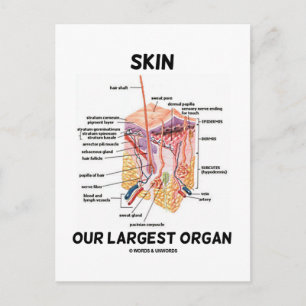

Cartão Postal Órgãos Internos